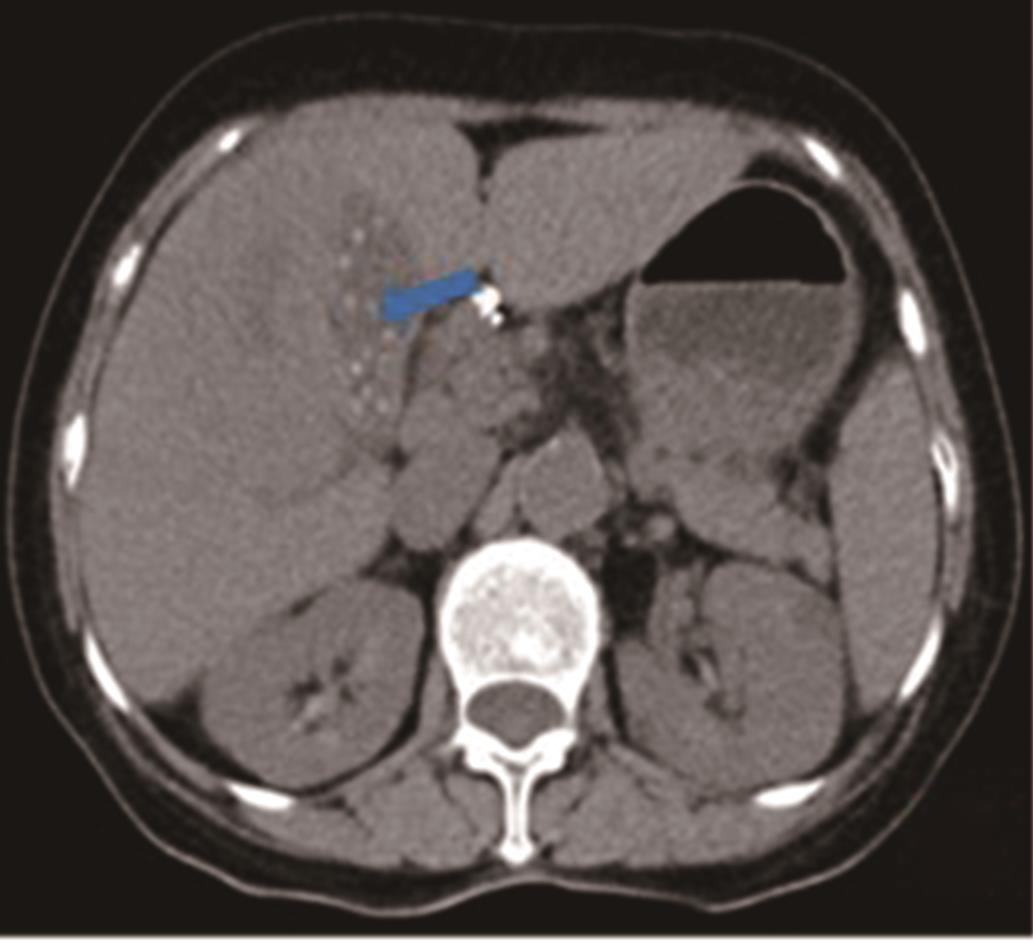

• 探讨增强CT在鉴别胆囊癌侵犯肝脏与肝癌累及胆囊病变中的应用价值

摘要:目的 探讨增强电子计算机断层扫描(computer tomography,CT)在胆囊癌侵犯肝脏与肝癌累及胆囊病变中的鉴别诊断价值。方法 收集2012年2月到2022年2月重庆医科大学附属第一医院115例患者临床及影像学资料,其中胆囊癌侵犯肝脏病例69例,肝癌累及胆囊病例46例,记录性别、年龄、肿瘤大小、肿瘤边界、胆囊形态、肝硬化、胆管扩张、肿瘤内或胆管系统内高密度影、门静脉癌栓、强化方式、强化程度、淋巴结肿大及远处转移共13个观察指标,并进行统计学分析。结果 性别(P=0.007)、年龄(P=0.002)、肿瘤大小(P=0.003)、肝硬化(P<0.001)、肿瘤内或胆管系统内高密度影(P=0.013)、门静脉癌栓(P<0.001)、强化方式(P<0.001)及淋巴结肿大(P=0.034)有统计学差异。通过回归分析筛选出年龄(敏感度为0.812,特异度为0.457)、肿瘤大小(敏感度为0.630,特异度为0.696)、门静脉癌栓(敏感度为0.326,特异度为0.957)、淋巴结肿大(敏感度为0.681,特异度为0.522)为显著分类指标,联合4个观察指标的参数绘制受试者工作特征(receiver operating characteristic,ROC)曲线,曲线下面积(area under the curve,AUC)为0.770,敏感度为0.674,特异度为0.826。结论 增强CT在鉴别胆囊癌侵犯肝脏与肝癌累及胆囊病变时,性别、年龄、肿瘤大小、肝硬化、肿瘤内或胆管系统内高密度影、门静脉癌栓、强化方式及淋巴结肿大有鉴别价值,同时结合年龄、肿瘤大小、门静脉癌栓及淋巴结肿大有助于提高鉴别诊断能力。